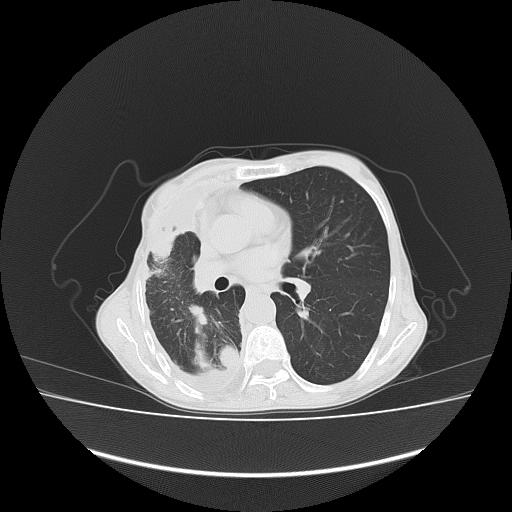

可见多发肺内病灶,且胸膜病灶较多有圆球状而非丘状,多考虑胸膜转移瘤伴胸腔积液,右侧胸廓缩小固定,且部分病灶呈丘状,尚不除外恶性胸膜间皮瘤伴肺内转移

右侧胸膜增厚,局部呈结节状增厚,右侧胸腔少量积液。双肺未见确切肿块影。纵隔未见淋巴结肿大。气管、支气管通畅。考虑右侧胸膜间皮瘤(恶性?)可能性大。不除外癌性胸膜炎。

右侧胸廓塌陷,右侧胸膜广泛增厚并见多发胸膜结节,右侧少量胸腔积液并包裹。

右侧广泛胸膜增厚,局部呈结节状增厚,右侧胸腔少量积液。双肺未见确切肿块影。纵隔未见淋巴结肿大。气管、支气管通畅。考虑右侧胸膜间皮瘤(恶性?)可能性大。支持!

右胸腔结节均考虑来自胸膜(部分来源于叶裂),考虑胸膜间皮瘤或转移瘤.